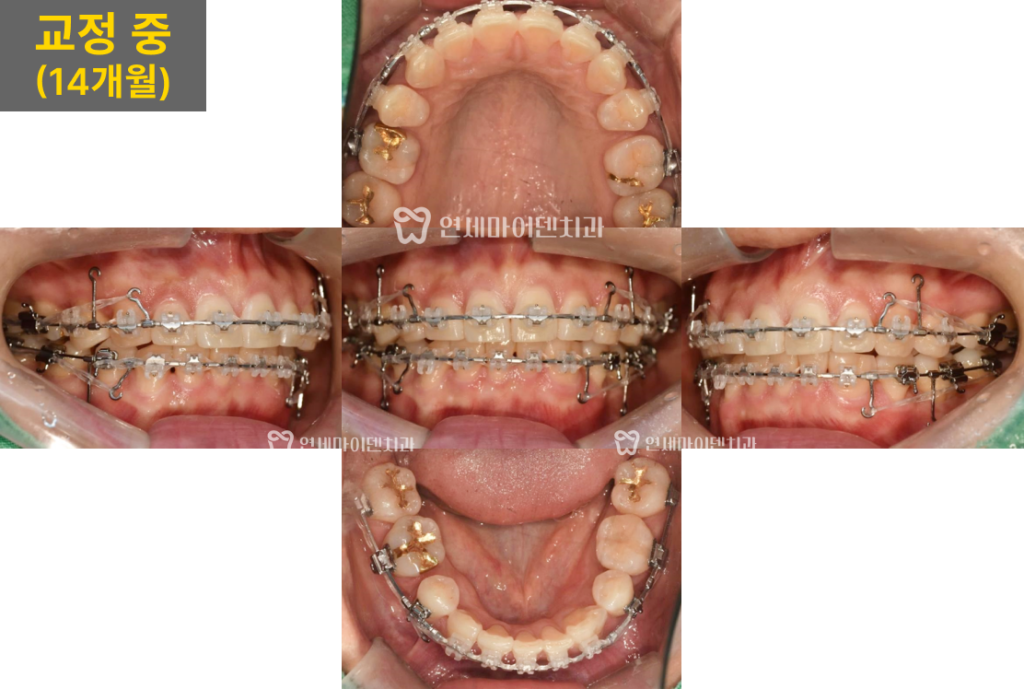

교정 시작 14개월 차에는 발치 공간이 점차 닫히면서

치아 배열이 안정화되었습니다.

또한, 아래 앞니의 치축도 바르게 세워지고

치우쳤던 중심선도 어느 정도 개선되었습니다.